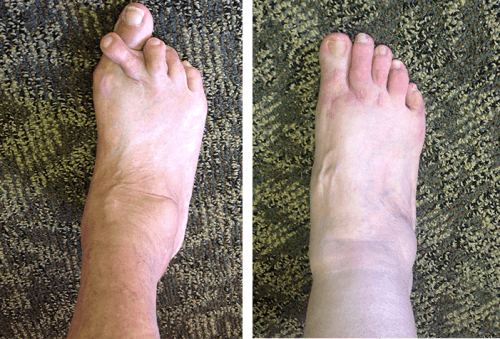

Guardate queste fotografie. Ecco cosa è successo a coloro che non hanno fatto attenzione ai sintomi. Oggi queste persone sono completamente senza speranza, e molti di loro non hanno nessuno su cui contare per le cure. Volete davvero un destino simile?

— Ognuna di queste persone pensava che non sarebbe mai successo a lei! Ma ecco il risultato: perdita totale di mobilità, paralisi, amputazione — dipendenza a vita dall’aiuto altrui e LA SEDIA A ROTELLE! Più del 90% diventa disabile solo perché non ha preso le giuste misure in tempo. L’USURA DELLE ARTICOLAZIONI INIZIA IN SILENZIO — ignorare il dolore significa buttare la propria vita nel secchio!